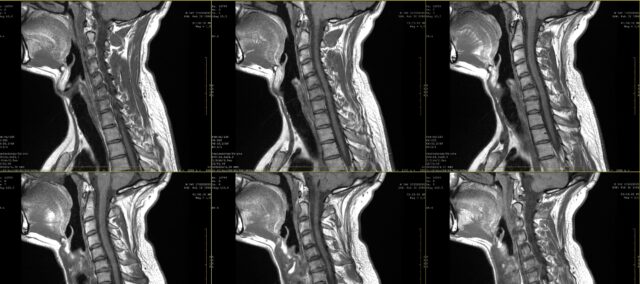

In der Schule haben Sie sicher etwas über Schmerzzeichnungen bei radikulären Schmerzen gelernt. Doch bereits im ersten Jahrzehnt des 21. Jahrhunderts wurde deutlich, dass radikuläre Schmerzen nicht unbedingt dermatomal verteilt sind. In dieser Studie sollte die Übereinstimmung zwischen der visuellen Inspektion von radikulären Schmerzzeichnungen, die von Patienten angefertigt wurden, und der MRT genauer untersucht werden. In der Praxis äußert ein Patient häufig seine Beschwerden, die durch eine Schmerzzeichnung ergänzt werden können. Bei Verdacht auf radikuläre Schmerzen werden häufig bildgebende Verfahren verordnet, um die betroffene Nervenwurzel und das Ausmaß der möglichen Nervenwurzelbeteiligung zu bestimmen. Obwohl dies in vielen Fällen Teil der Routinepraxis ist, wissen wir nicht, bis wir die Übereinstimmung zwischen diesen Schmerzzeichnungen und der betroffenen Nervenwurzel kennen, die mittels MRT bestimmt wurde. In dieser Studie untersuchten Marco et al. (2023) verglichen radikuläre Schmerzzeichnungen und MRT-Befunde.

Um die Übereinstimmung zwischen Zeichnungen von radikulären Schmerzen und MRT-Befunden zu untersuchen, wurden in diese Studie Teilnehmer mit einer 2-monatigen Anamnese von anhaltenden Schmerzen aufgenommen, bei denen im MRT eine zervikale Radikulopathie diagnostiziert wurde. Diese Diagnose wurde von einem Neurochirurgen auf der Grundlage der klinischen Informationen und der von einem Radiologen bewerteten MRT-Befunde gestellt.